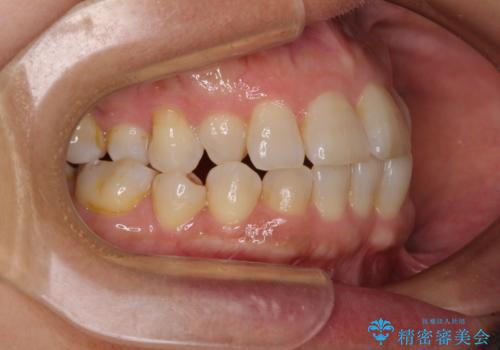

骨格のずれをカムフラージュ クロスバイトのワイヤー矯正

- 骨格的な咬み合わせのズレ、前歯のデコボコとクロスバイトを気にして来院された患者様です。

奥歯の噛みにくさが顕著なためマウスピースではなく、ワイヤー装置による矯正治療を行うこととしました。

下顎の正中を歯1本分ずらした位置とすることで、外見上の骨格的なずれをカバーするように計画しました。

クロスバイトを改善したことで、前歯の負担が軽減し、安定して噛めるようになりました。